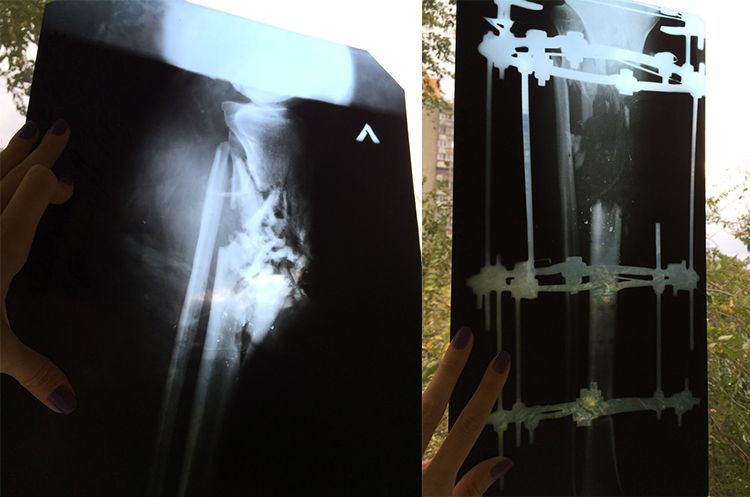

Вогнепальне поранення лівої великогомілкової кістки з дефектом кістки до 14 см

реконструктивно-відновлювальне лікування великогомілкової кістки з використанням клітинних технологій.

Боєць переніс кілька операцій, його травма була ускладнена післятравматичним остеомієлітом та розвитком гнилостної інфекції, а зараз частина лівої великогомілкової кістки фактично відсутня.

Єдина можливість відновити такий дефект та повернути нозі опороздатність – складне хірургічне лікування з використанням клітинних технологій.

У червні 2015 року була проведена основна операція з відновлення великогомілкової кістки. Під час операції виявили проблему у гомілково-ступневому суглобі, що потребує виконання додаткової операції з артродезу суглобу. Вартість операції: 64 569 грн